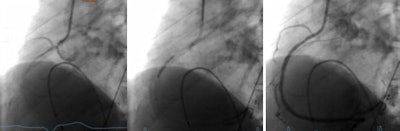

Major adverse events such as ST-elevated myocardial infarction (STEMI), non-ST-elevated myocardial infarction (NSTEMI), and cardiac death served as the primary study endpoints, while coronary revascularization procedures like percutaneous coronary intervention (PCI) or coronary artery bypass graft (CABG) served as secondary endpoints.

"We do see a shift towards increasing referrals of asymptomatic patients with high-risk profile to CCTA -- from many cardiologists," he wrote. The feedback from interventional cardiologists along with this trend is very positive though. Catheterization lab cardiologists recently reported relatively increasing numbers in positive procedures and reducing number of diagnostic caths -- which is a very positive trend for both patients and physicians. Not everyone is on board with CT referrals for everyone at high risk, however.

The group plans to continue its follow-up of the study patients, and will probably add fractional flow reserve-CT, which has shown a lot of promise in assessing the severity of stenosis, to future exams, he said.